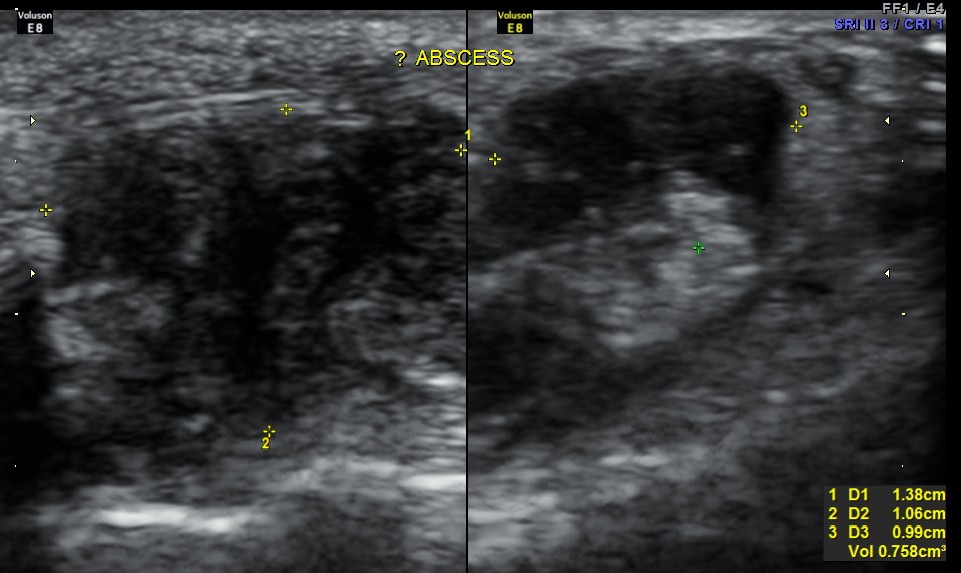

Ultrasound done with high resolution transducer revealed the following findings :

An indistinct hypo echoic mass was seen under a tendon and was well away from the surface of the bone .

A diagnosis of an abscess in formation was offered and the child recovered well with appropriate treatment.

The following are the pictures.